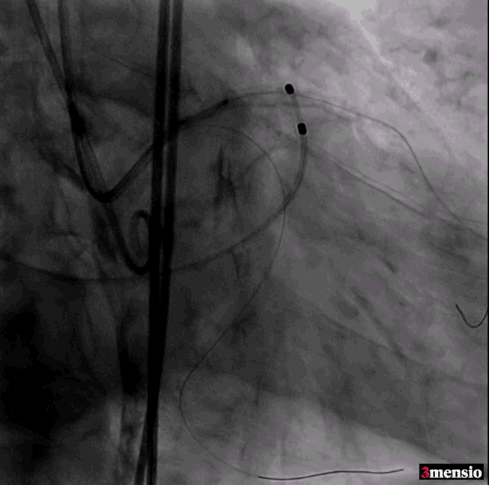

标准位释放定位

23mm球囊后扩

术后造影

瓣膜定位精准,标准位释放,轻微瓣周漏,术后效果良好,手术取得圆满成功。